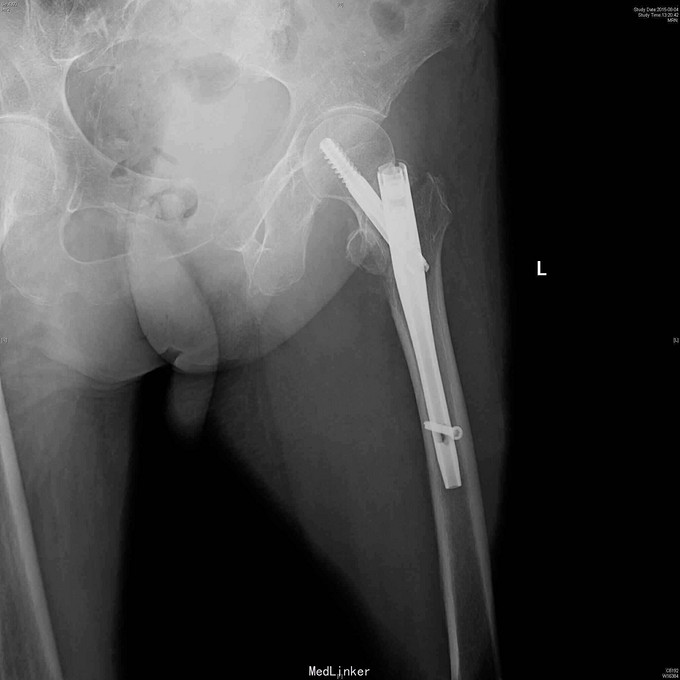

诊断:左股骨粗隆间骨折 治疗:左股骨粗隆间骨折闭合复位髓内钉固定术。术后抗凝4周,预防骨质疏松治疗。

随访:8周后复诊,左髋无明显不适,屈髋自如,已部分负重行走。 讨论:股骨粗隆间骨折最佳治疗方法是闭合牵引复位近端髓内钉固定,预后都不错。对于老年人,骨质疏松明显,容易发生腰椎,髋关节和桡骨远端等部位的骨质疏松压缩骨折,所以术后应当重视骨质疏松方面的治疗并坚持。一起讨论一下该例手术存在的不足和治疗老年人骨折方面的经验。